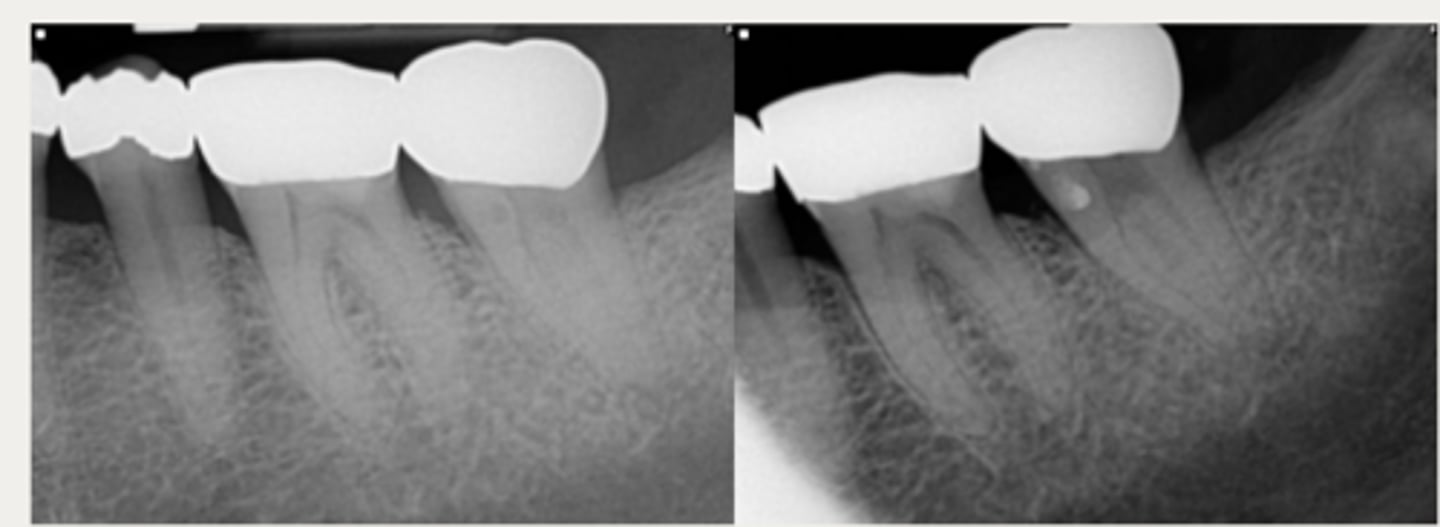

External cervical resorption (Invasive Cervical Resorption)

ID the type of resorption:

- Often asymptomatic until late stages, and may be misdiagnosed as caries

- Possible pink spot in the cervical aspect of the tooth, near gingival margin

- Often hemorrhagic on probing

- Feels hard and scratchy when probed (unlike subgingival caries which feels sticky)

- Usually an incidental radiographic finding, especially for less advanced lesions

- Variable appearances; may be a well-defined or irregular radiolucency around the cervical aspect of the tooth

- A portal of entry is always present in the cervical region of the tooth

- The chamber/canal outline is often visible as the innermost layer of predentin around the chamber is not resorbed

Patient presents with these radiographic findings, what type of resorption?

- Incidental finding

- Radiolucency around cervical aspect of tooth

- Portal of entry present in cervical region

- Chamber/canal outline is visible

What type of lesion is similar to internal resorption but is distinguished by taking an off-angle PA in which the lesion moves?